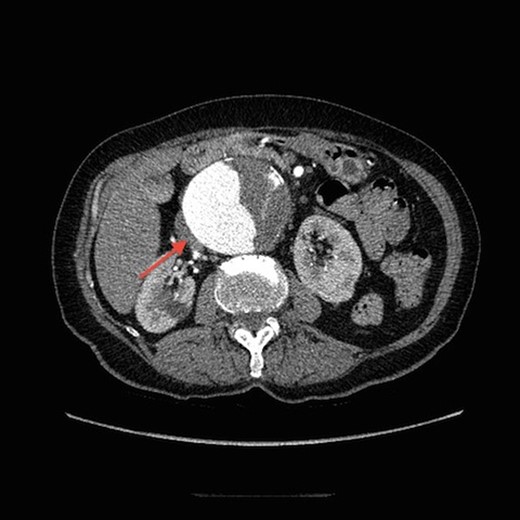

On arrival at our hospital, she was hemodynamically stable, with all vital signs within the normal range. Abdominal examination revealed a pulsating mass in the center of the abdomen. A computed tomography (CT) angiogram of aorta was performed for further evaluation that showed ectatic aorta from arch to the diaphragm. There was an 8.7-cm infra-abdominal AAA with extension into both common iliac arteries. The aneurysm neck was tortuous with an acute angle making endovascular repair challenging (Figs 1–4).

Transverse view of CT aortogram, showing compression of IVC (arrow).